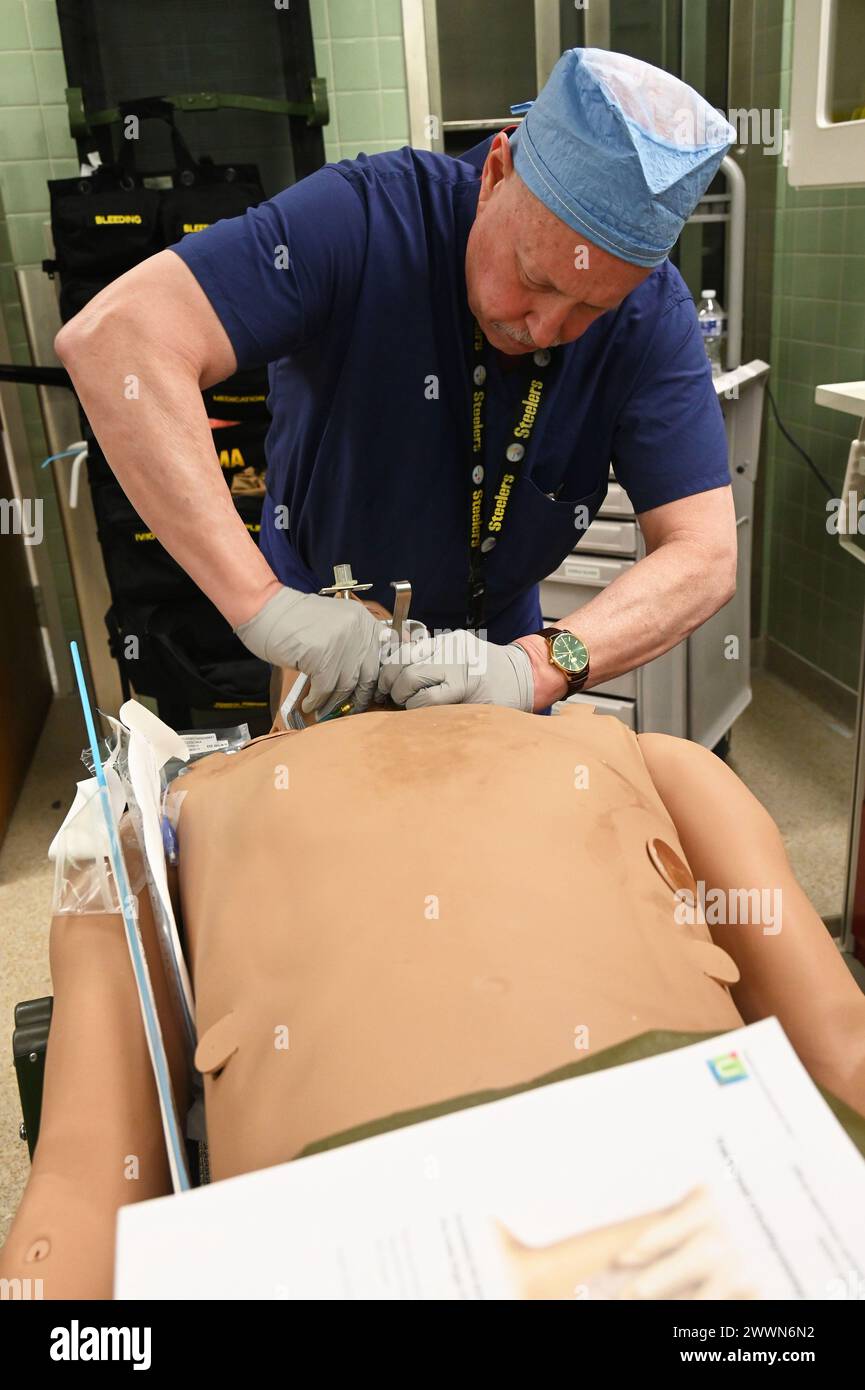

U.S. Army Sgt. Connor Lauster, assigned to C Company, 15th Brigade Support Battalion, 2nd Armored Brigade Combat Team, 1st Cavalry Division, conducts tactical field care at the Medical Simulation Training Center, on Fort Cavazos, Texas, February 22, 2024. At this stage, Lauster is checking his casualty for hemorrhage, airway obstruction, and circulatory issues. Army Stock Photohttps://www.alamy.com/image-license-details/?v=1https://www.alamy.com/us-army-sgt-connor-lauster-assigned-to-c-company-15th-brigade-support-battalion-2nd-armored-brigade-combat-team-1st-cavalry-division-conducts-tactical-field-care-at-the-medical-simulation-training-center-on-fort-cavazos-texas-february-22-2024-at-this-stage-lauster-is-checking-his-casualty-for-hemorrhage-airway-obstruction-and-circulatory-issues-army-image601012350.html

U.S. Army Sgt. Connor Lauster, assigned to C Company, 15th Brigade Support Battalion, 2nd Armored Brigade Combat Team, 1st Cavalry Division, conducts tactical field care at the Medical Simulation Training Center, on Fort Cavazos, Texas, February 22, 2024. At this stage, Lauster is checking his casualty for hemorrhage, airway obstruction, and circulatory issues. Army Stock Photohttps://www.alamy.com/image-license-details/?v=1https://www.alamy.com/us-army-sgt-connor-lauster-assigned-to-c-company-15th-brigade-support-battalion-2nd-armored-brigade-combat-team-1st-cavalry-division-conducts-tactical-field-care-at-the-medical-simulation-training-center-on-fort-cavazos-texas-february-22-2024-at-this-stage-lauster-is-checking-his-casualty-for-hemorrhage-airway-obstruction-and-circulatory-issues-army-image601012350.htmlRM2WWPDAP–U.S. Army Sgt. Connor Lauster, assigned to C Company, 15th Brigade Support Battalion, 2nd Armored Brigade Combat Team, 1st Cavalry Division, conducts tactical field care at the Medical Simulation Training Center, on Fort Cavazos, Texas, February 22, 2024. At this stage, Lauster is checking his casualty for hemorrhage, airway obstruction, and circulatory issues. Army

The Kimbrough Ambulatory Care Center Anesthesia Care Team simulated various methods of performing an emergency cricothyrotomy, Fort Meade, Maryland, Feb. 5, to validate providers' skills and update credentials. A cricothyrotomy is an incision made through the skin and cricothyroid membrane to establish a patent airway during certain life-threatening situations, such as airway obstruction by a foreign body, angioedema, or massive facial trauma. Defense Health Agency Stock Photohttps://www.alamy.com/image-license-details/?v=1https://www.alamy.com/the-kimbrough-ambulatory-care-center-anesthesia-care-team-simulated-various-methods-of-performing-an-emergency-cricothyrotomy-fort-meade-maryland-feb-5-to-validate-providers-skills-and-update-credentials-a-cricothyrotomy-is-an-incision-made-through-the-skin-and-cricothyroid-membrane-to-establish-a-patent-airway-during-certain-life-threatening-situations-such-as-airway-obstruction-by-a-foreign-body-angioedema-or-massive-facial-trauma-defense-health-agency-image600985198.html

The Kimbrough Ambulatory Care Center Anesthesia Care Team simulated various methods of performing an emergency cricothyrotomy, Fort Meade, Maryland, Feb. 5, to validate providers' skills and update credentials. A cricothyrotomy is an incision made through the skin and cricothyroid membrane to establish a patent airway during certain life-threatening situations, such as airway obstruction by a foreign body, angioedema, or massive facial trauma. Defense Health Agency Stock Photohttps://www.alamy.com/image-license-details/?v=1https://www.alamy.com/the-kimbrough-ambulatory-care-center-anesthesia-care-team-simulated-various-methods-of-performing-an-emergency-cricothyrotomy-fort-meade-maryland-feb-5-to-validate-providers-skills-and-update-credentials-a-cricothyrotomy-is-an-incision-made-through-the-skin-and-cricothyroid-membrane-to-establish-a-patent-airway-during-certain-life-threatening-situations-such-as-airway-obstruction-by-a-foreign-body-angioedema-or-massive-facial-trauma-defense-health-agency-image600985198.htmlRM2WWN6N2–The Kimbrough Ambulatory Care Center Anesthesia Care Team simulated various methods of performing an emergency cricothyrotomy, Fort Meade, Maryland, Feb. 5, to validate providers' skills and update credentials. A cricothyrotomy is an incision made through the skin and cricothyroid membrane to establish a patent airway during certain life-threatening situations, such as airway obstruction by a foreign body, angioedema, or massive facial trauma. Defense Health Agency

The Kimbrough Ambulatory Care Center Anesthesia Care Team simulated various methods of performing an emergency cricothyrotomy, Fort Meade, Maryland, Feb. 5, to validate providers' skills and update credentials. A cricothyrotomy is an incision made through the skin and cricothyroid membrane to establish a patent airway during certain life-threatening situations, such as airway obstruction by a foreign body, angioedema, or massive facial trauma. Defense Health Agency Stock Photohttps://www.alamy.com/image-license-details/?v=1https://www.alamy.com/the-kimbrough-ambulatory-care-center-anesthesia-care-team-simulated-various-methods-of-performing-an-emergency-cricothyrotomy-fort-meade-maryland-feb-5-to-validate-providers-skills-and-update-credentials-a-cricothyrotomy-is-an-incision-made-through-the-skin-and-cricothyroid-membrane-to-establish-a-patent-airway-during-certain-life-threatening-situations-such-as-airway-obstruction-by-a-foreign-body-angioedema-or-massive-facial-trauma-defense-health-agency-image600985589.html

The Kimbrough Ambulatory Care Center Anesthesia Care Team simulated various methods of performing an emergency cricothyrotomy, Fort Meade, Maryland, Feb. 5, to validate providers' skills and update credentials. A cricothyrotomy is an incision made through the skin and cricothyroid membrane to establish a patent airway during certain life-threatening situations, such as airway obstruction by a foreign body, angioedema, or massive facial trauma. Defense Health Agency Stock Photohttps://www.alamy.com/image-license-details/?v=1https://www.alamy.com/the-kimbrough-ambulatory-care-center-anesthesia-care-team-simulated-various-methods-of-performing-an-emergency-cricothyrotomy-fort-meade-maryland-feb-5-to-validate-providers-skills-and-update-credentials-a-cricothyrotomy-is-an-incision-made-through-the-skin-and-cricothyroid-membrane-to-establish-a-patent-airway-during-certain-life-threatening-situations-such-as-airway-obstruction-by-a-foreign-body-angioedema-or-massive-facial-trauma-defense-health-agency-image600985589.htmlRM2WWN771–The Kimbrough Ambulatory Care Center Anesthesia Care Team simulated various methods of performing an emergency cricothyrotomy, Fort Meade, Maryland, Feb. 5, to validate providers' skills and update credentials. A cricothyrotomy is an incision made through the skin and cricothyroid membrane to establish a patent airway during certain life-threatening situations, such as airway obstruction by a foreign body, angioedema, or massive facial trauma. Defense Health Agency

The Kimbrough Ambulatory Care Center Anesthesia Care Team simulated various methods of performing an emergency cricothyrotomy, Fort Meade, Maryland, Feb. 5, to validate providers' skills and update credentials. A cricothyrotomy is an incision made through the skin and cricothyroid membrane to establish a patent airway during certain life-threatening situations, such as airway obstruction by a foreign body, angioedema, or massive facial trauma. Defense Health Agency Stock Photohttps://www.alamy.com/image-license-details/?v=1https://www.alamy.com/the-kimbrough-ambulatory-care-center-anesthesia-care-team-simulated-various-methods-of-performing-an-emergency-cricothyrotomy-fort-meade-maryland-feb-5-to-validate-providers-skills-and-update-credentials-a-cricothyrotomy-is-an-incision-made-through-the-skin-and-cricothyroid-membrane-to-establish-a-patent-airway-during-certain-life-threatening-situations-such-as-airway-obstruction-by-a-foreign-body-angioedema-or-massive-facial-trauma-defense-health-agency-image600985568.html

The Kimbrough Ambulatory Care Center Anesthesia Care Team simulated various methods of performing an emergency cricothyrotomy, Fort Meade, Maryland, Feb. 5, to validate providers' skills and update credentials. A cricothyrotomy is an incision made through the skin and cricothyroid membrane to establish a patent airway during certain life-threatening situations, such as airway obstruction by a foreign body, angioedema, or massive facial trauma. Defense Health Agency Stock Photohttps://www.alamy.com/image-license-details/?v=1https://www.alamy.com/the-kimbrough-ambulatory-care-center-anesthesia-care-team-simulated-various-methods-of-performing-an-emergency-cricothyrotomy-fort-meade-maryland-feb-5-to-validate-providers-skills-and-update-credentials-a-cricothyrotomy-is-an-incision-made-through-the-skin-and-cricothyroid-membrane-to-establish-a-patent-airway-during-certain-life-threatening-situations-such-as-airway-obstruction-by-a-foreign-body-angioedema-or-massive-facial-trauma-defense-health-agency-image600985568.htmlRM2WWN768–The Kimbrough Ambulatory Care Center Anesthesia Care Team simulated various methods of performing an emergency cricothyrotomy, Fort Meade, Maryland, Feb. 5, to validate providers' skills and update credentials. A cricothyrotomy is an incision made through the skin and cricothyroid membrane to establish a patent airway during certain life-threatening situations, such as airway obstruction by a foreign body, angioedema, or massive facial trauma. Defense Health Agency

The Kimbrough Ambulatory Care Center Anesthesia Care Team simulated various methods of performing an emergency cricothyrotomy, Fort Meade, Maryland, Feb. 5, to validate providers' skills and update credentials. A cricothyrotomy is an incision made through the skin and cricothyroid membrane to establish a patent airway during certain life-threatening situations, such as airway obstruction by a foreign body, angioedema, or massive facial trauma. Defense Health Agency Stock Photohttps://www.alamy.com/image-license-details/?v=1https://www.alamy.com/the-kimbrough-ambulatory-care-center-anesthesia-care-team-simulated-various-methods-of-performing-an-emergency-cricothyrotomy-fort-meade-maryland-feb-5-to-validate-providers-skills-and-update-credentials-a-cricothyrotomy-is-an-incision-made-through-the-skin-and-cricothyroid-membrane-to-establish-a-patent-airway-during-certain-life-threatening-situations-such-as-airway-obstruction-by-a-foreign-body-angioedema-or-massive-facial-trauma-defense-health-agency-image600987065.html

The Kimbrough Ambulatory Care Center Anesthesia Care Team simulated various methods of performing an emergency cricothyrotomy, Fort Meade, Maryland, Feb. 5, to validate providers' skills and update credentials. A cricothyrotomy is an incision made through the skin and cricothyroid membrane to establish a patent airway during certain life-threatening situations, such as airway obstruction by a foreign body, angioedema, or massive facial trauma. Defense Health Agency Stock Photohttps://www.alamy.com/image-license-details/?v=1https://www.alamy.com/the-kimbrough-ambulatory-care-center-anesthesia-care-team-simulated-various-methods-of-performing-an-emergency-cricothyrotomy-fort-meade-maryland-feb-5-to-validate-providers-skills-and-update-credentials-a-cricothyrotomy-is-an-incision-made-through-the-skin-and-cricothyroid-membrane-to-establish-a-patent-airway-during-certain-life-threatening-situations-such-as-airway-obstruction-by-a-foreign-body-angioedema-or-massive-facial-trauma-defense-health-agency-image600987065.htmlRM2WWN93N–The Kimbrough Ambulatory Care Center Anesthesia Care Team simulated various methods of performing an emergency cricothyrotomy, Fort Meade, Maryland, Feb. 5, to validate providers' skills and update credentials. A cricothyrotomy is an incision made through the skin and cricothyroid membrane to establish a patent airway during certain life-threatening situations, such as airway obstruction by a foreign body, angioedema, or massive facial trauma. Defense Health Agency